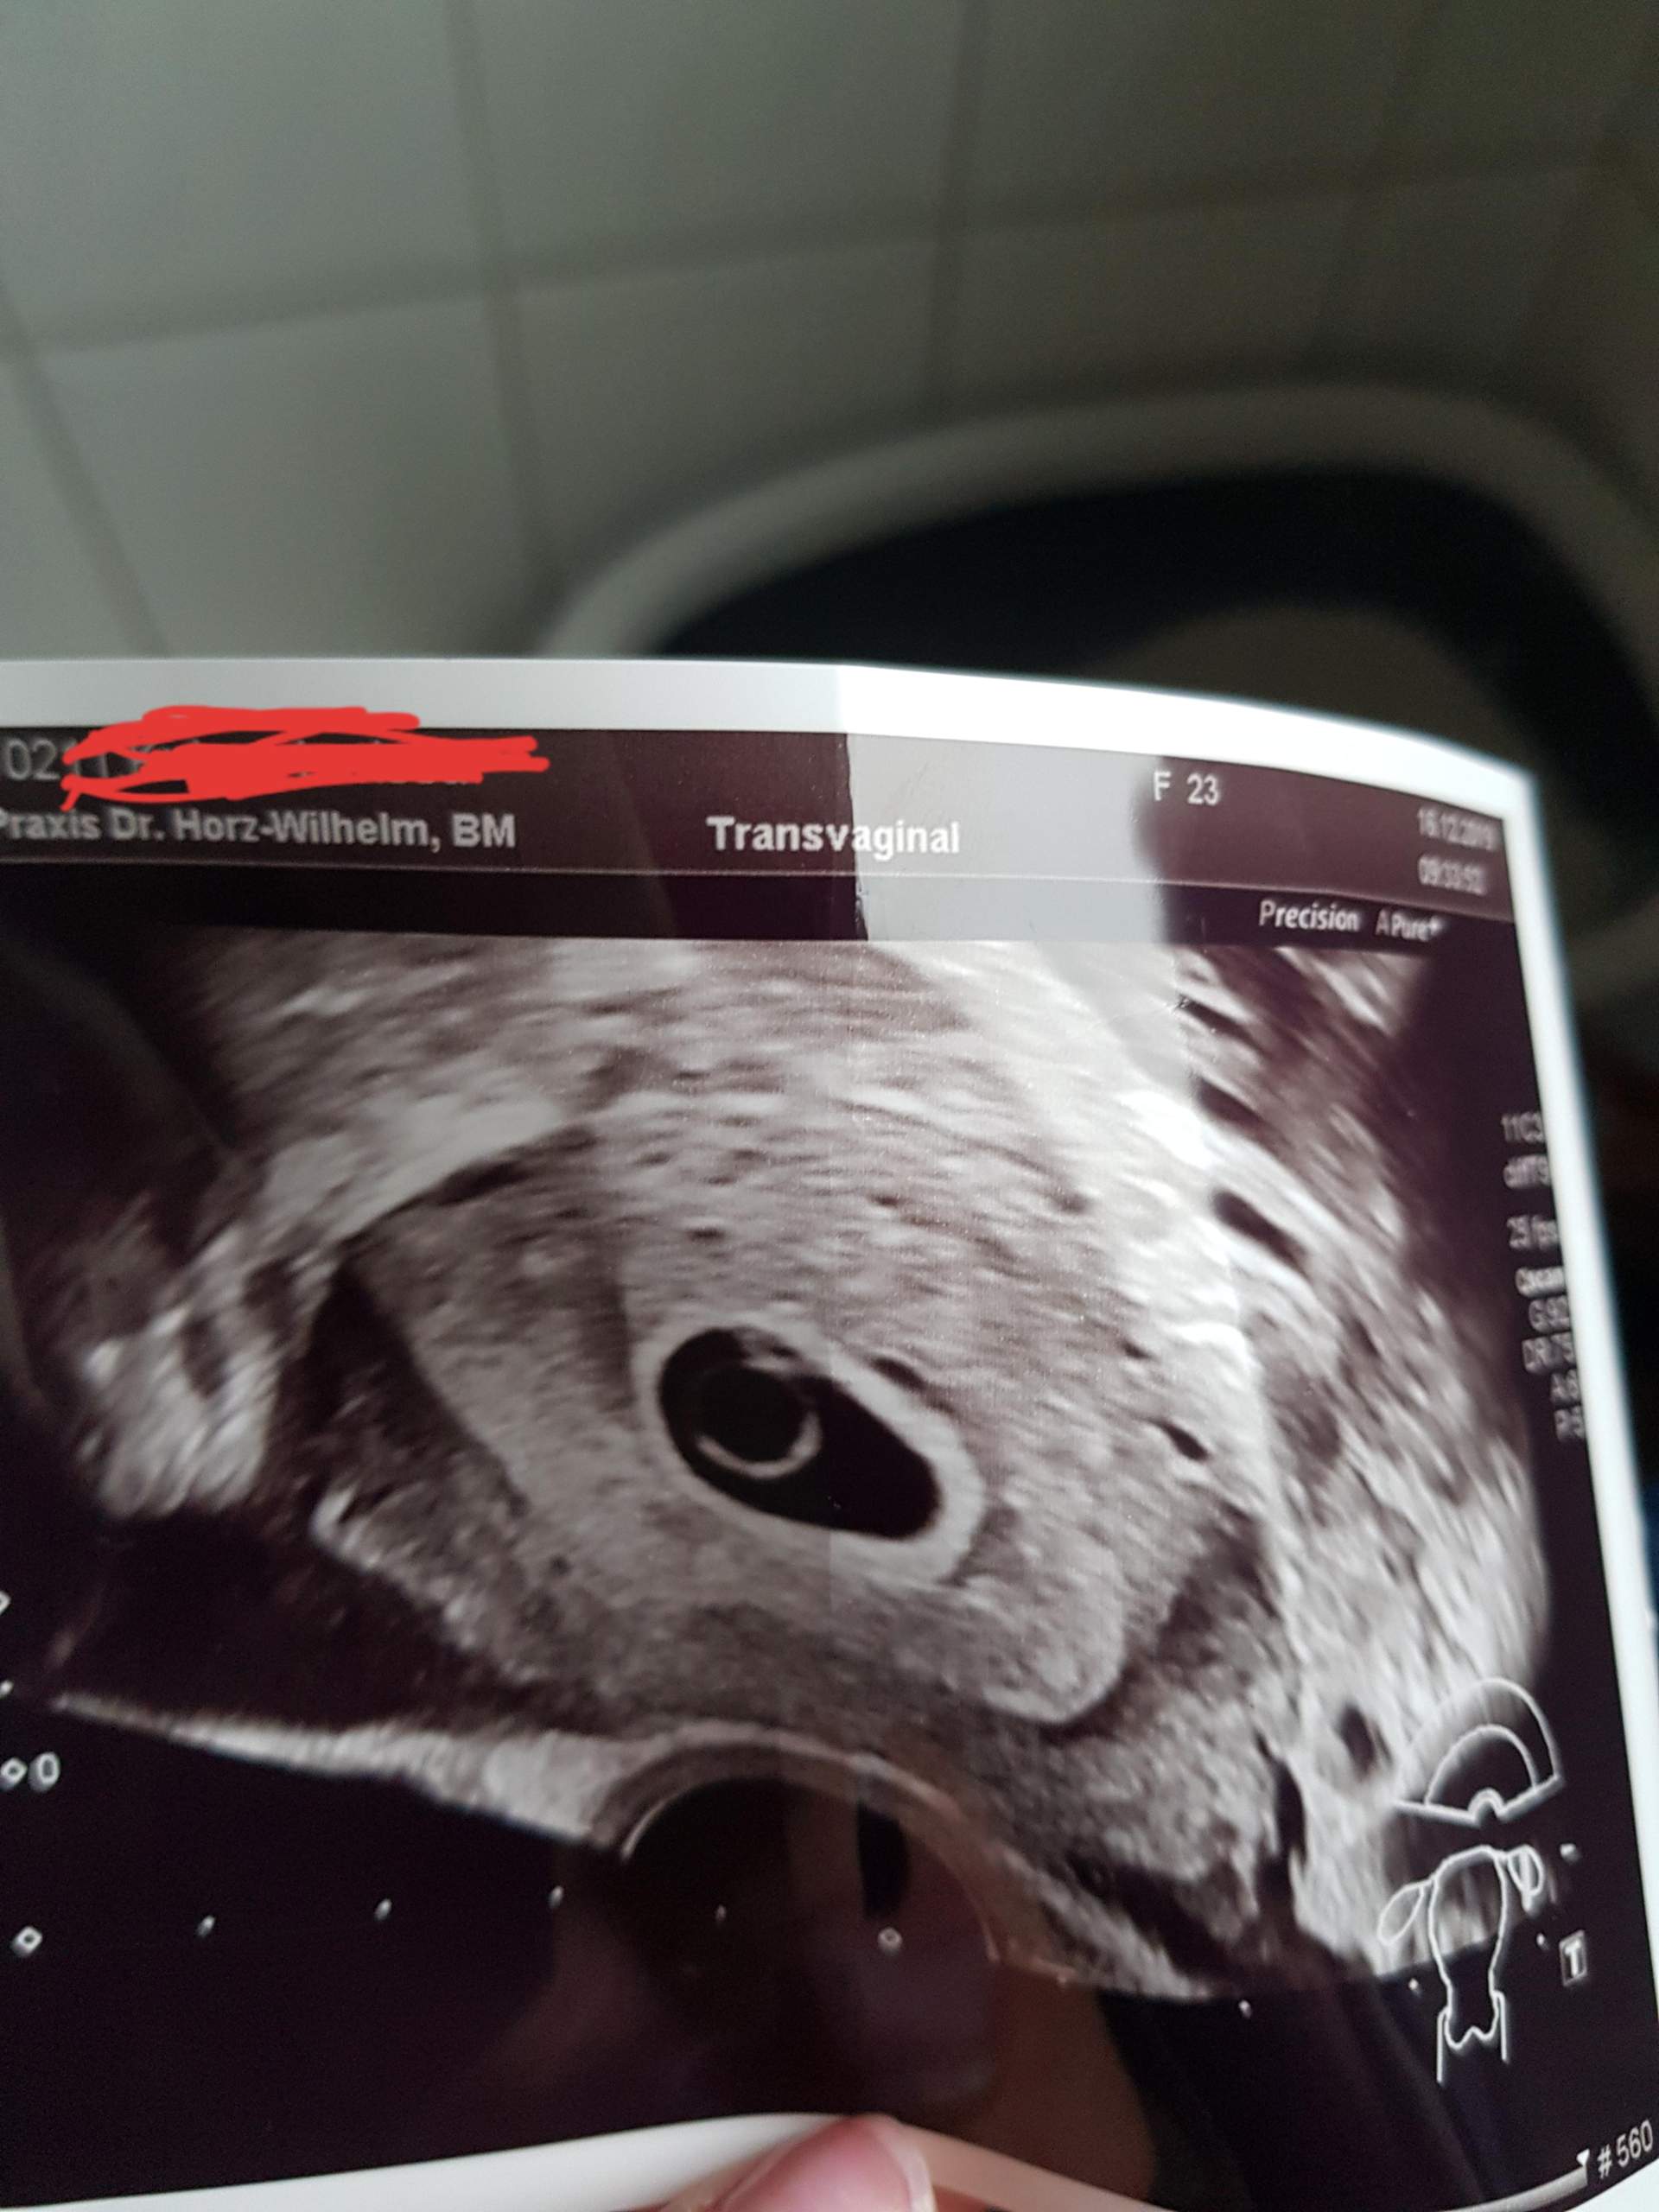

5 2 Ssw Schwangerschaft Ultraschall